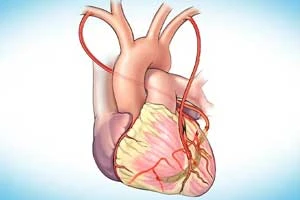

CABG (Coronary Artery Bypass Grafting)

Advanced bypass surgery to restore blood flow to heart

CABG (Coronary Artery Bypass Grafting)

Advanced bypass surgery to restore blood flow to heart